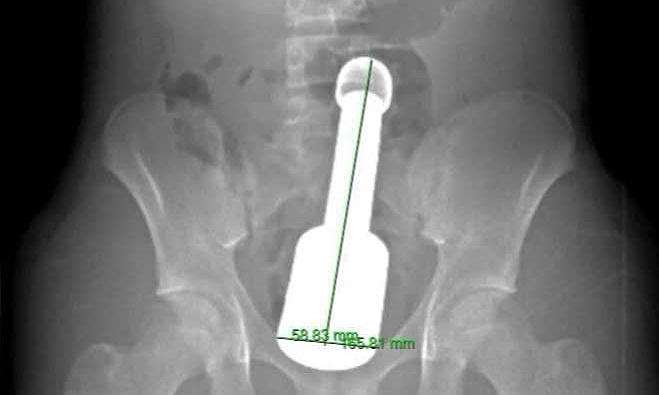

X-ray image showing the foreign object in the rectum. *Photo: Hospital provided* |

The male student was previously admitted to the emergency room suffering from severe lower abdominal pain. Doctors examined him, where they found a large foreign object deeply lodged in the rectum, compressing nearby pelvic organs. The reason and context for the student's actions are currently unknown.

The biggest challenge for the surgical team was the pestle's size, which exceeded the anal sphincter's maximum capacity for a teenager. The object's size and weight created a "vacuum effect," causing the intestinal wall to grip its surface tightly. Pure pulling force would have posed a high risk of perineal tearing or rectal rupture.